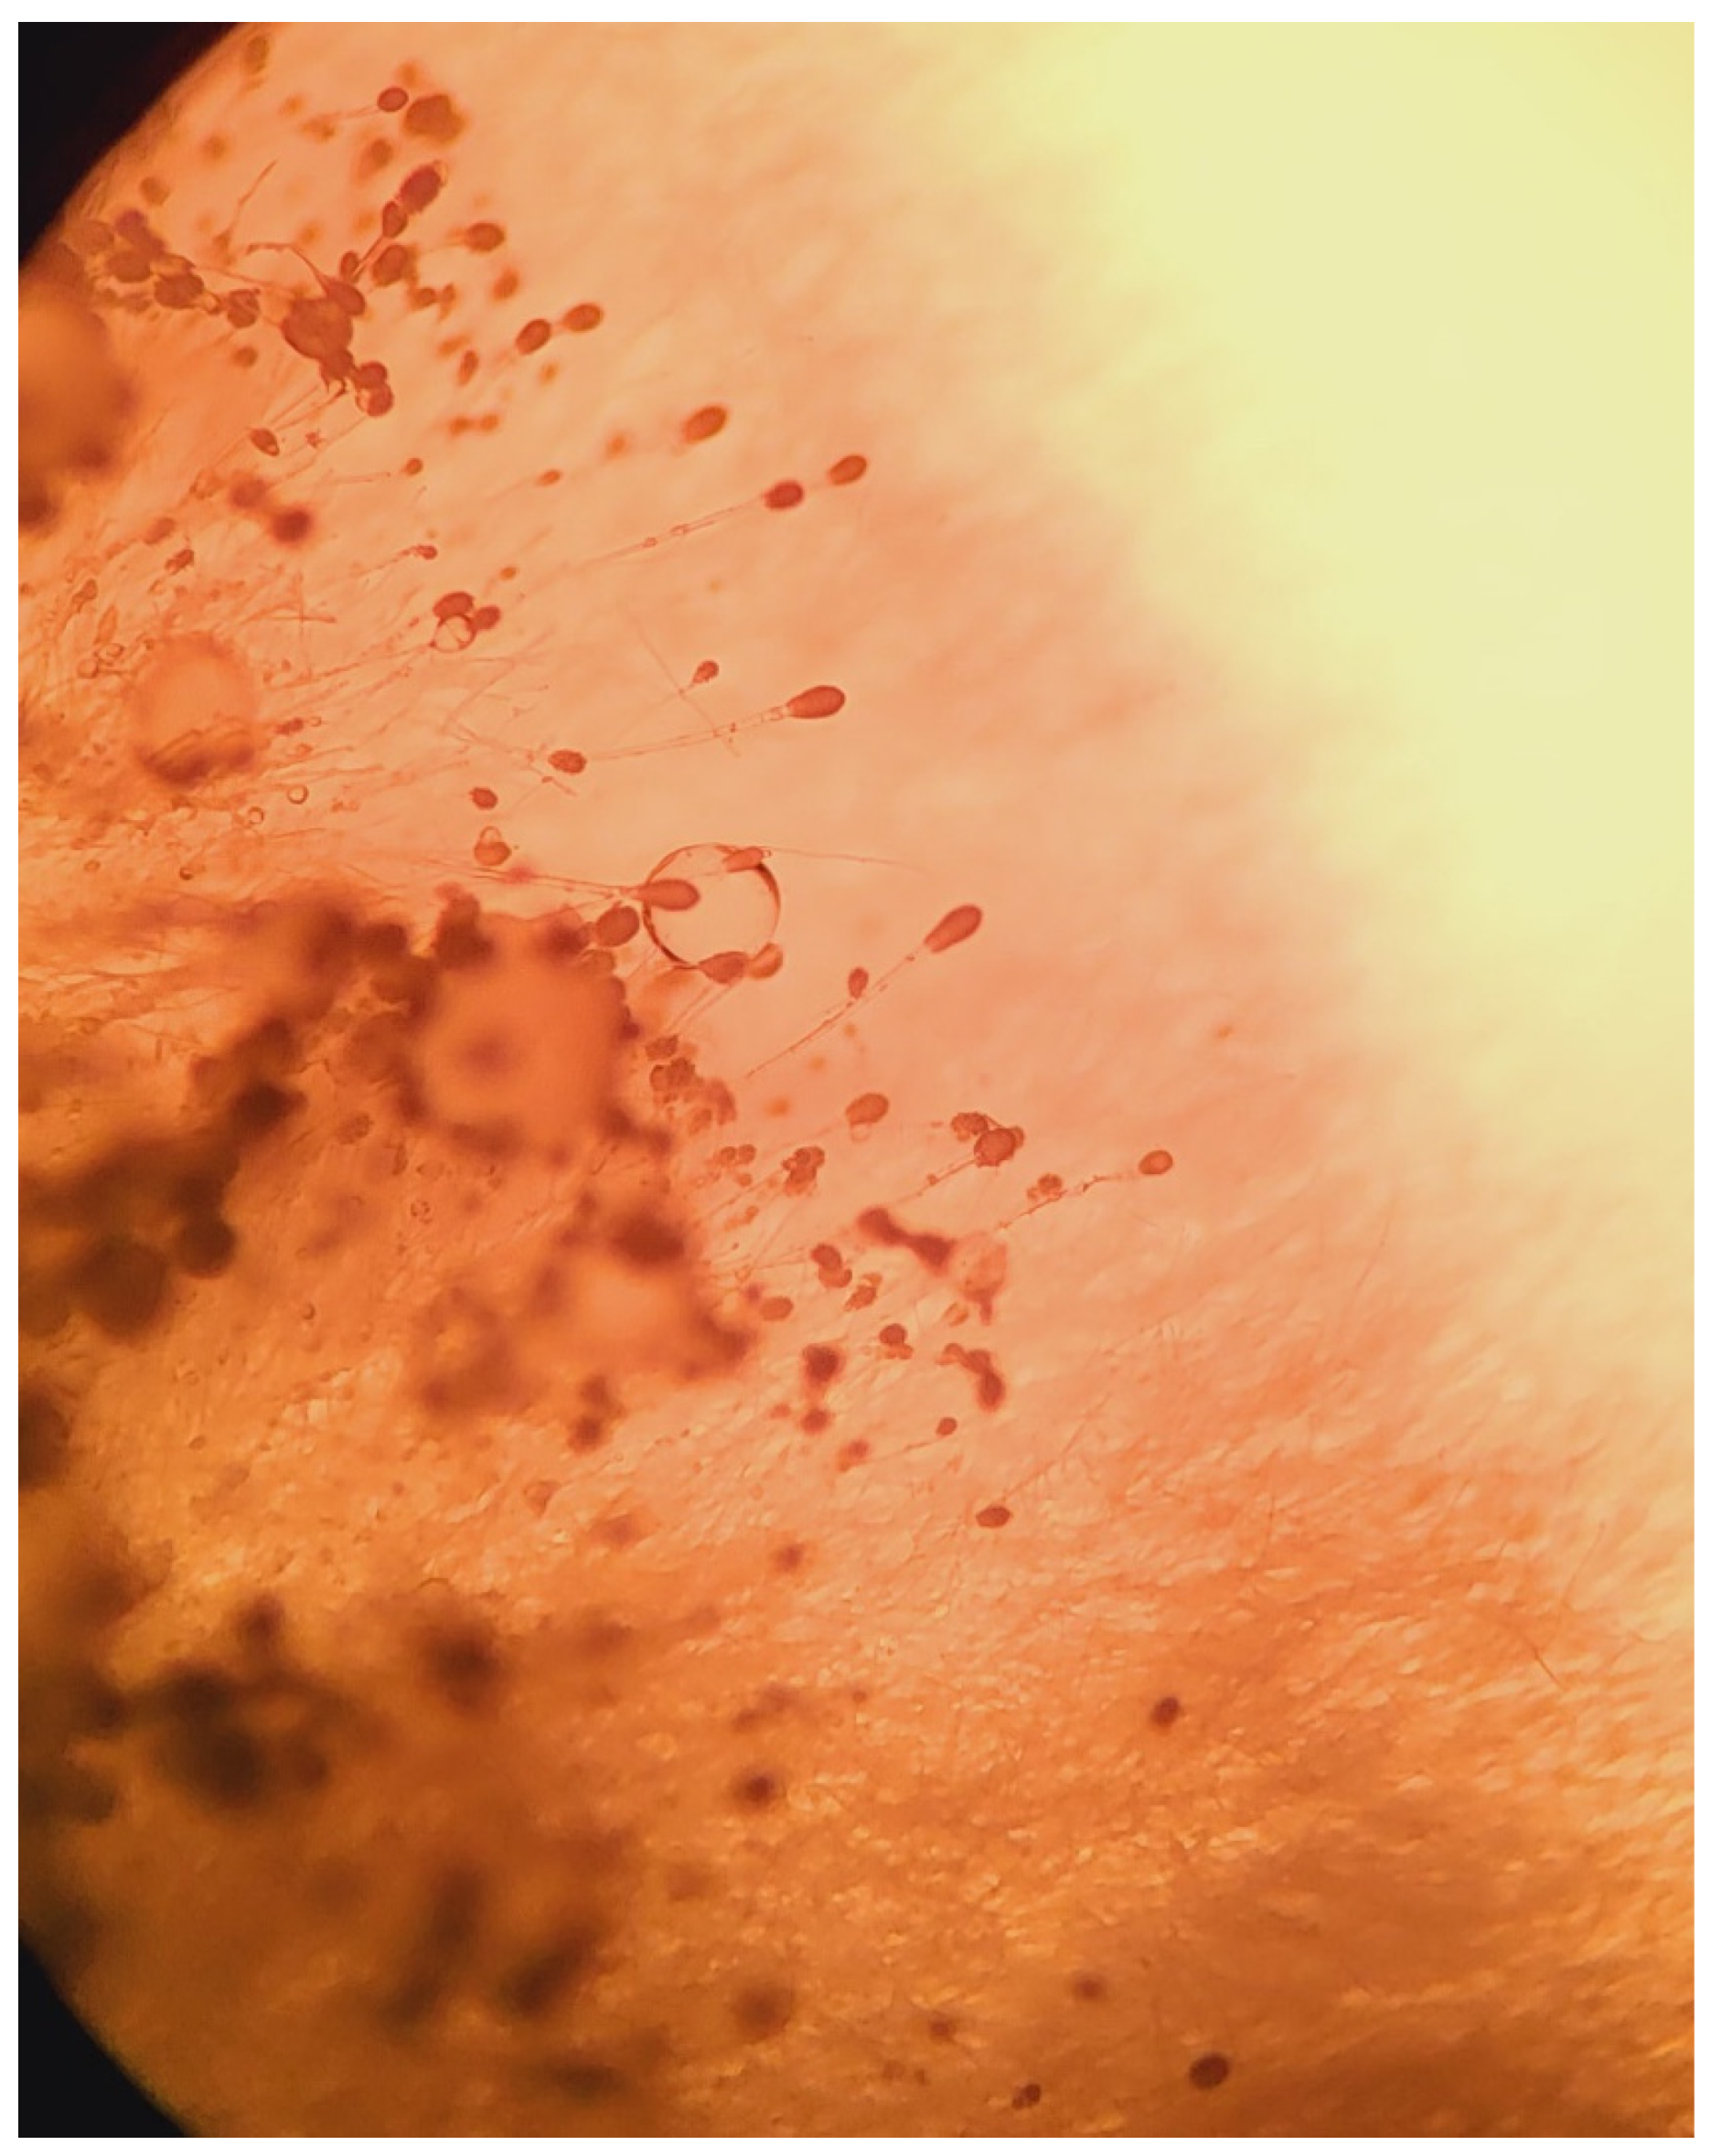

Once the Sabouraud broth turned turbid, the material was subcultured onto Sabouraud agar with gentamicin and chloramphenicol. After 3 days, growth was detected. Aerial mycelia (Figure 1) were subjected to identification based on the detailed analysis of colony pigmentation, morphology of the hyphae, and the shape/size of conidiophores after being stained with lactophenol cotton blue, and observed under a light microscope at a 400-time magnification (Figure 2) using an Olympus CH20BMF200 microscope. The microscopic analysis revealed characteristic clavate-shaped conidiophores (Figure 3).

Figure 2.

Clavate-shaped conidiophores of A. clavatus at 400× magnification, lactophenol cotton blue wet mount preparation.